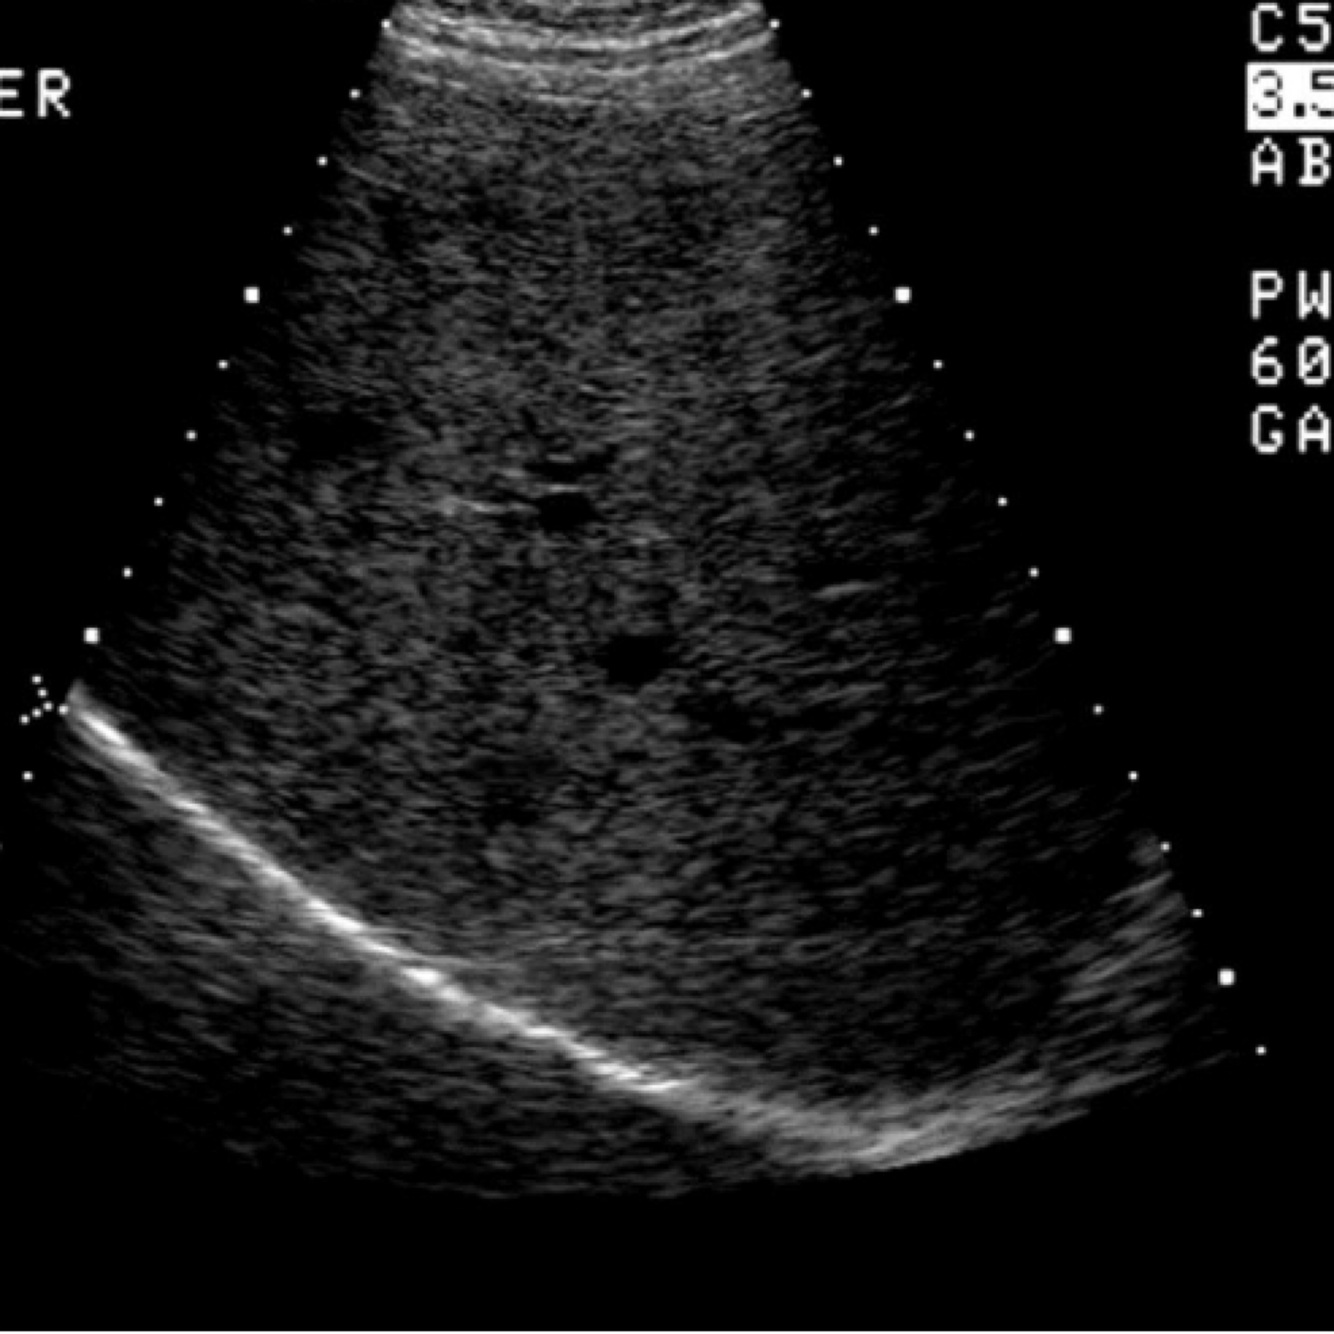

What does this image demonstrate?

Propagation speed error

79

Propagation speed error *Look at the diaphragm*

80